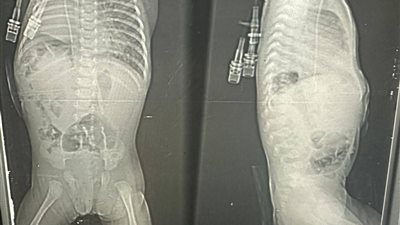

نفسه يلعب ويتحرك زي زمايله.. والد الصغير أمير مريض ضمور العضلات يستغيث لعلاجه| فيديو

ملناش حد في الدنيا.. والدة صغير مريض بضمور العضلات تستغيث لعلاجه: محتاج 13 مليون جنيه وحساباته قربت تتقفل